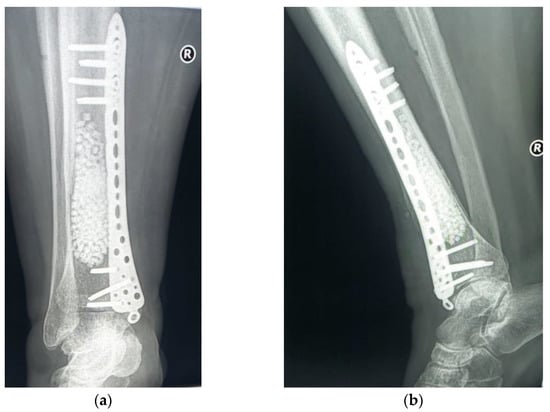

As bone strength was diminished by tumor erosion of the cortex, there was a risk of fracture. Thus, safety osteosynthesis, using one plate (titanium alloy) with locked screws was associated (Figure 10).

Figure 10. Curettage, bone substitute grafting and plate osteosynthesis. After surgery radiographs (a) Radiological, coronal view; (b) Radiological, lateral view.